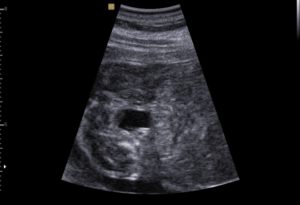

УЗ-диагностику беременным женщинам проводят трижды. Но если возникает необходимость, врач может назначить дополнительное исследование для подтверждения или исключения диагноза.

На каждом из плановых УЗИ доктор смотрит как выглядит плод. Соответствует ли голова, ноги, руки, живот, нос тому этапу развития, на котором находится малыш. На более поздних сроках врач выявляет какие органы развиты правильно: сердце, желудок, печень и пр.

Что можно выявить в первом триместре?

Во время первого УЗИ можно определить риск развития синдрома Дауна и некоторых других хромосомных патологий. Самое главное, чтобы плод был определенного размера.

Измеряется КТР (копчиково-теменной размер), он должен быть не меньше 45 мм, но и не больше 84 мм.

Если плод будет слишком маленький или наоборот большой, то будет невозможно трактовать такой показатель как толщина воротникового пространства или зоны (ТВП).

На скрининге первого триместра можно выявить некоторые хромосомные заболевания плода

Толщина воротниковой зоны – это толщина всех тканей в области шеи. В норме этот показатель не превышает 2,7 мм, а среднее значение 1,6 мм. Если размер воротниковой зоны больше 3 мм, то вероятность наличия синдрома Дауна у плода очень большая.